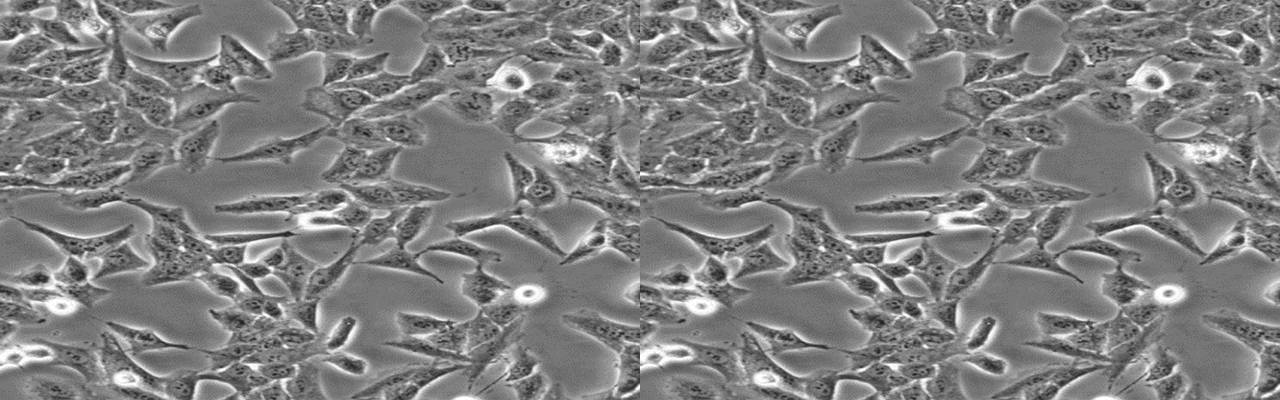

| 细胞全名 | NCI-H446 [H446](人小细胞肺癌细胞) |

| 生长特性: | 贴壁/悬浮 |

背景资料:NCI-H446细胞是从一位小细胞肺癌患者的胸水中建立的,NCI-H446细胞的原始形态并不具有小细胞肺癌特征。NCI-H446细胞是小细胞肺癌的生化和形态学上的变种,表达神经元特有的烯醇酶和脑部肌酸激酶同功酶。NCI-H446细胞内左旋多巴脱羧酶、蚕素、抗利尿激素、催产素或胃泌激素释放肽未达到可检测水平。C-myc DNA序列扩增约20倍,c-myc RNA比正常细胞增加15倍。最初,传代培养基用RPMI-1640(含5%胎牛血清、10nM氢化可的松、0.005mg/ml胰岛素、0.01mg/ml铁传递蛋白、10nM 17-β-雌二醇、30nM亚硒酸钠)。